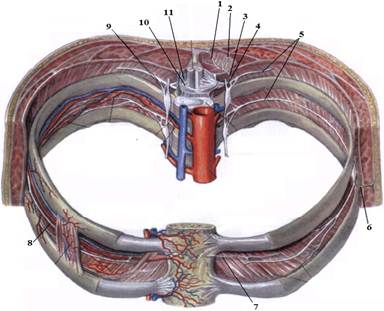

1. Яким номером позначено N. thoracicus?

2. Яким номером позначено N. intercostalis?

3. Яким номером позначено R. cutaneus lateralis?

4. Яким номером позначено R. dorsalis n. thoracici?

5. Яким номером позначено R. cutaneus lateralis r.dorsalis n. thoracici?

6. Яким номером позначено R. cutaneus medialis r.dorsalis n. thoracici?

7. Яким номером позначено R. cutaneus anterior?

8. Яким номером позначено Rr.communicantes n. thoracici?

9. Яким номером позначено Radix dorsalis n. thoracici?

10. Яким номером позначено Radix ventralis n. thoracici?

На таблицях і трупах студенти знаходять судинно-нервового пучка міжребрового проміжку. Далі на трупі розглядають хід і розподіл грудних нервів та ділянки їх інервації, Користуючись таблицями вивчають лімфатичні судини і вузли грудної клітки. На трупі ззаду і справа від грудної аорти знаходять грудну протоку. Визначають її корені хід топографію. На таблицях вивчають корені правої лімфатичної протоки визначають ділянки відпливу до двох головних лімфатичних проток.Викладач консультує студентів по темі заняття, показує незрозумілі деталі будови. В кінці заняття викладач шляхом тестування кінцевого рівня знань та вмінь оцінює роботу кожного студента в академічному журналі.